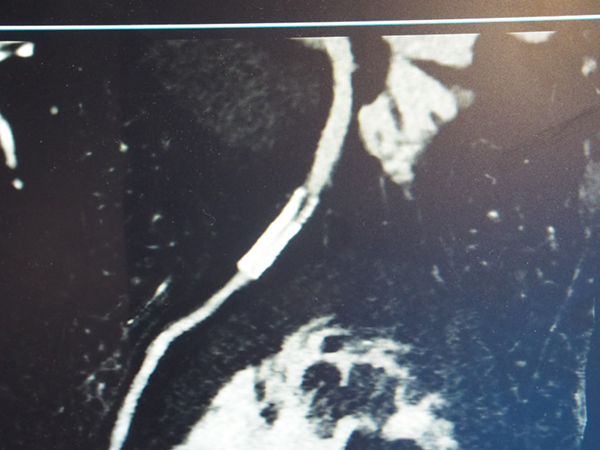

また,CT装置によってはDual Energy撮影の撮影範囲が限定されることがあるが,IQonシリーズは通常通り撮影した画像からDual Energy解析を行うため,撮影範囲に特別な制限はない。会場では,腕の外傷による救急症例で,受傷部だけでなく全身状態を評価するために上肢と体幹部を一緒に撮影し,後からMonoEで造影効果を向上させる処理を施した症例が紹介された。約45cmの広い範囲も問題なく撮影できており,緊急時にも短時間で高度な検査画像を提供できることが示された。

IQonシリーズでは広範囲(約45cm)のDual Energy解析も可能